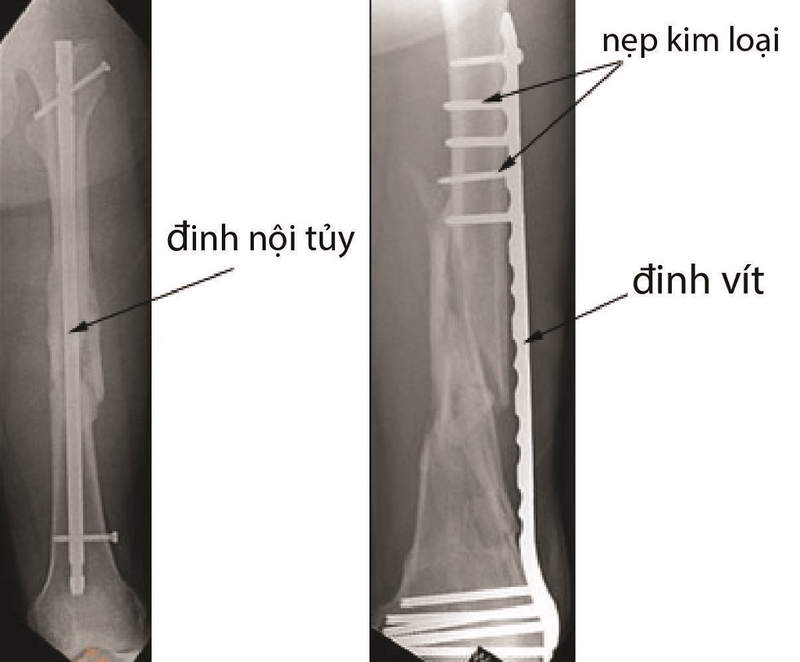

Có hai phương pháp chính thường được sử dụng trong phẫu thuật kết hợp xương, đó là kết hợp xương bằng đinh nội tủy và sử dụng nẹp vít.

Thường được ưu tiên áp dụng cho bệnh nhân gãy từ 1/3 thân xương chi dưới, đặc biệt là ở những xương ống dài như xương đùi, xương chày, do đinh nội tủy có khả năng chịu lực tỷ lớn, mà chi dưới phải chịu đựng trọng lực lớn khi cơ thể thực hiện các hoạt động vận động và đi lại.

Ngoài ra, phương pháp này cũng được áp dụng trong các trường hợp gãy xương ở trẻ em, đặc biệt là khi có độ di lệch lớn và không thể điều trị bằng băng nẹp hoặc bó bột. Quyết định sử dụng loại đinh nội tủy cụ thể như Kuntscher, đinh Rush, đinh SIGN, đinh Metaizeau sẽ phụ thuộc vào tình trạng cụ thể của vết thương và thời gian từ khi xảy ra tình trạng gãy xương.